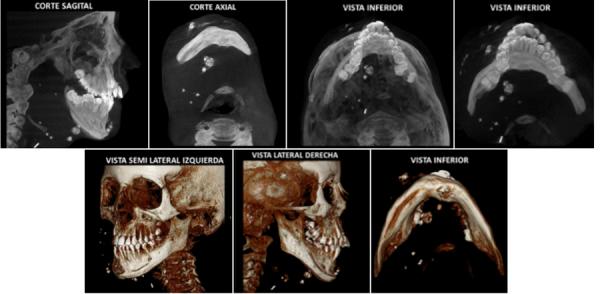

Vascular alterations or disorders of the blood and / or lymphatic vessels have their own characteristics, the identification of calcifications being a correct parameter to be able to make a proper diagnosis. The objective of the study was to describe the radiographic characteristics of the phleboliths, and whether they represent a challenge for diagnosis. according to the literature reviewed in the Medline (PubMed) database, Scielo, Google Scholar and some specialized journals. Phleboliths were found to have very particular radiographic characteristics, with concentric radiolucent and radiopaque images that resemble rings. However, not all the presentations are similar, this makes the diagnosis misleading with other calcifications in this region, such as sialoliths where their appearance is usually similar. Furthermore, there is the relationship with vascular anomalies and hemangiomas. finally, the evidence points to very specific characteristics of this lesion, and it is necessary to individualize each case, due to the differences that exist from one patient to another.

血管改变或血液及/或淋巴管疾病有其自身特点,钙化的识别是能够做出正确诊断的一个正确参数。本研究的目的是描述静脉石的影像学特征,以及它们是否对诊断构成挑战。根据在Medline(PubMed)数据库、Scielo、谷歌学术以及一些专业期刊中检索到的文献。发现静脉石具有非常特殊的影像学特征,有类似环状的同心透射线和不透射线图像。然而,并非所有表现都相似,这使得在该区域与其他钙化(如涎石,其外观通常相似)的诊断产生混淆。此外,还存在与血管异常和血管瘤的关系。最后,证据表明该病变具有非常特殊的特征,由于不同患者之间存在差异,有必要对每个病例进行个体化分析。